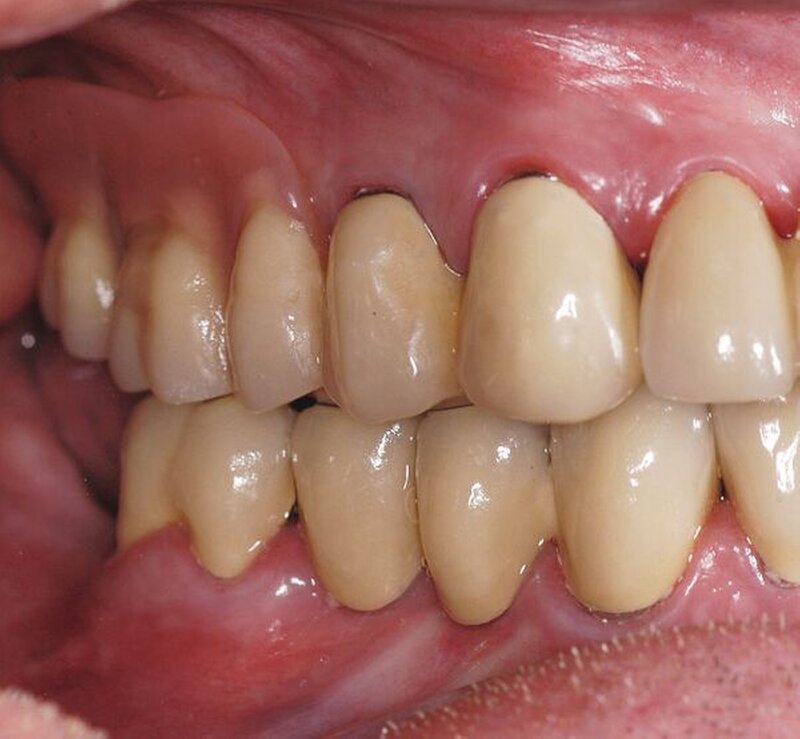

Im Rahmen der intraoralen Befunderhebung wurde festgestellt, dass die Gingiva insgesamt gerötet und ödematös war. Die Messung der Taschentiefe ergab einen durchschnittlichen Wert von fünf mm. Der ermittelte PSI (in Bezug auf die Sechstanten) ergab die Werte 4, 2, 4, 3, 2, 2. Pusaustritt konnte in regio 17 und in regio 27 festgestellt werden, so dass der Erhalt dieser Zähne fraglich war. Im Oberkiefer lag ein prothetisch versorgtes Lückengebiss der Kennedy-Klasse III2 vor. Die Zähne 18, 16, 15, 11, 25, 26 und 28 fehlten. Die prothetische Versorgung bestand aus einer Brücke 17 bis 14 zum Ersatz von 16 und 15, einer Brücke 13 bis 23 zum Ersatz von 11 und einer Brücke 24 bis 27 zum Ersatz von 25 und 26. Sämtliche Brückenanker wiesen Randundichtigkeiten und Sekundärkariesbildung auf. An 21 konnte eine großflächige Keramikabplatzung festgestellt werden. 17 und 27 reagierten im Perkussionstest stark positiv. Im Rahmen einer Sensibilitätsprüfung mittels CO2-Schnee reagierten die Zähne 17, 22 und 27 negativ. Im Unterkiefer lag ein Gebiss der Kennedy-Klasse II3 vor. Die Zähne 38, 36, 34, 44, 45, 47 und 48 fehlten. Die Zähne 37, 42, 46 waren mit Füllungen versorgt, die erhebliche Undichtigkeiten aufwiesen. 46 reagierte im Kältetest negativ. Alle Unterkieferzähne wiesen starke Attritionen auf. Diese Zähne 33 bis 43 sowie 37 und 35 reagierten im Kältetest stark schmerzhaft (Abbildungen 4, 5).

Mit dem Patienten wurden verschiedene Therapiealternativen diskutiert. Durch die werkstofftechnischen Rahmenbedingungen und die finanziellen Vorgaben entschlossen wir uns dazu, im Unterkiefer eine festsitzende Versorgung mittels zweier vollverblendeter VMK-Brücken von 37 bis 35 und von 43 bis 46 sowie vier vollverblendeter VMK-Einzelkronen (32 bis 42) anzustreben. Im Oberkiefer erfolgte die Planung im Sinne einer kombiniert festsitzend-herausnehmbaren Versorgung: vollverblendete VMK-Brücke 12 bis 21, vollverblendete VMK-Einzelkrone 22, Extraktion von 17 und 27, teleskopierend verankerte partielle Prothese mit den Pfeilerzähnen 14, 13, 23 und 24 (Abbildungen 6, 7, 8, 9, 10a, 10b, 11).